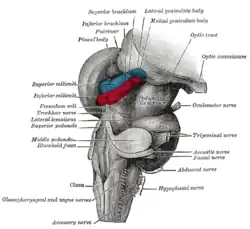

Axial section of the pons, at its upper part Hind- and mid-brains; posterolateral view

Hind- and mid-brains; posterolateral view Median sagittal section of brain